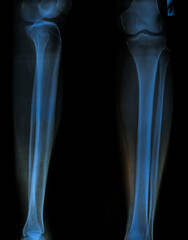

Podobny obraz Medical Elbow Anterior View X-Ray Radiograph Illustrating...